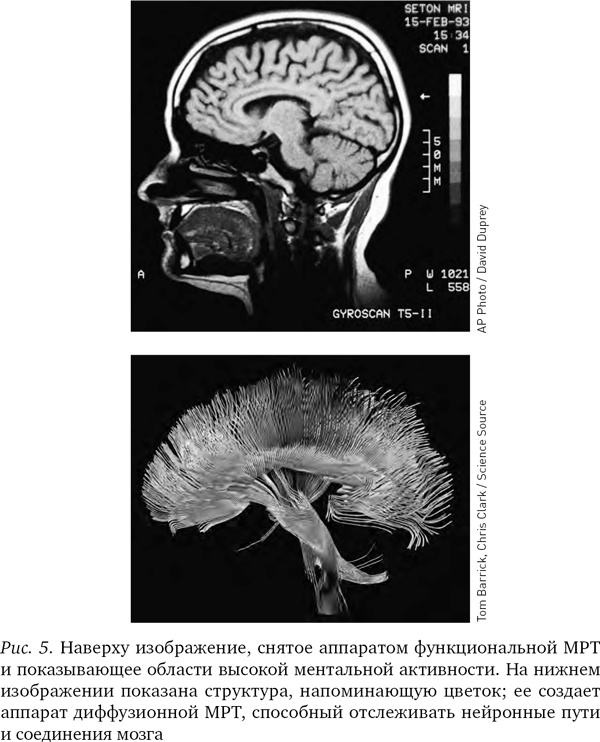

МРТ-изображения опровергли представление о том, что мышление сосредоточено в едином центре. Напротив, можно видеть, что в процессе мышления электрическая энергия циркулирует по различным частям мозга. Отслеживая путь, который проходят мысли в голове человека, МРТ-аппараты помогли пролить свет на природу болезней Альцгеймера и Паркинсона, шизофрении и других психических заболеваний.

Серьезным преимуществом МРТ-аппаратов является то, что они могут с высокой точностью выделять крохотные, вплоть до десятых долей миллиметра, участки мозга и рассматривать их отдельно. МРТ-изображение — не просто точки на двумерном экране (пикселы), а точки в трехмерном пространстве (вокселы): в результате исследования мы получаем яркое трехмерное изображение мозга, сложенное из десятков тысяч цветных точек.

Различные химические элементы реагируют на разные частоты радиоволн по-разному, поэтому мы можем, изменяя частоту волны, определять, где какие элементы находятся. Как уже отмечалось, при фМРТ в основном отслеживаются атомы кислорода в крови и измеряют кровоток, но вообще-то аппарат МРТ можно настроить на любое вещество. В последнее десятилетие появилась новая разновидность МРТ — диффузионно-тензорная; она отслеживает движение воды в объеме мозга. Вода в мозге следует по нейронным путям, поэтому диффузионно-тензорная томография позволяет получить красивые картинки, напоминающие переплетение растущих в саду лиан. Теперь ученые могут мгновенно определить, как части мозга связаны между собой.

Иллюстрация к книге — Будущее разума [i_005.jpg]